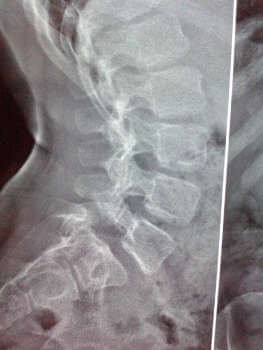

Ακτινολογικός έλεγχος όπου εμφανίζεται ολίσθηση του υπερκείμενου σπονδύλου σε σχέση με τον υποκείμενο και διακρίνεται η διάσπαση του τόξου στις λοξές ακτινογραφίες της ΟΜΣΣ.

Εικόνα Ακτινολογική εικόνα σπονδυλολίσθησης Ο5 - Ι1